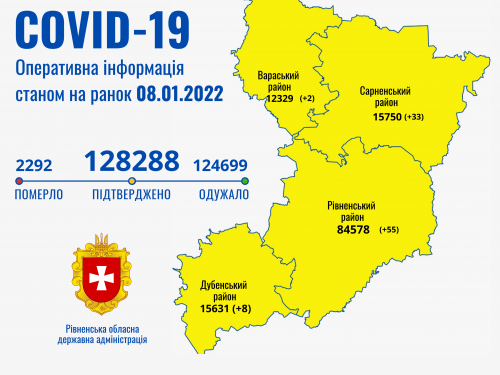

Коронавірус повертається: як стрімко зростає кількість хворих на Рівненщині (ВІДЕО)